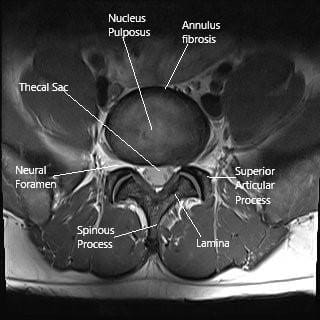

Una resonancia magnética muestra la sección axial de la columna lumbar con foramen neural estrechamiento.

El saco dural que contiene todas las raíces nerviosas de la cauda equina se encuentra dentro del conducto central. El conducto central está delimitado por el cuerpo vertebral y el disco intervertebral intermedio en la parte frontal y la lámina en la parte trasera. Las articulaciones facetarias están presentes cerca del foramen neural en los lados del conducto vertebral.